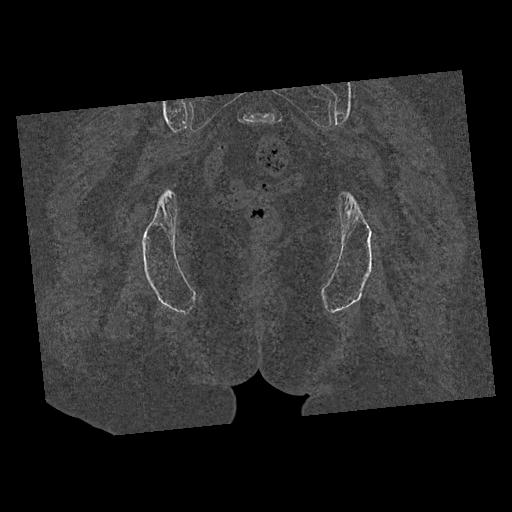

100703 1/27 両股正面+軸 1/29 両股正面+軸 94歳女性 パンソンロン